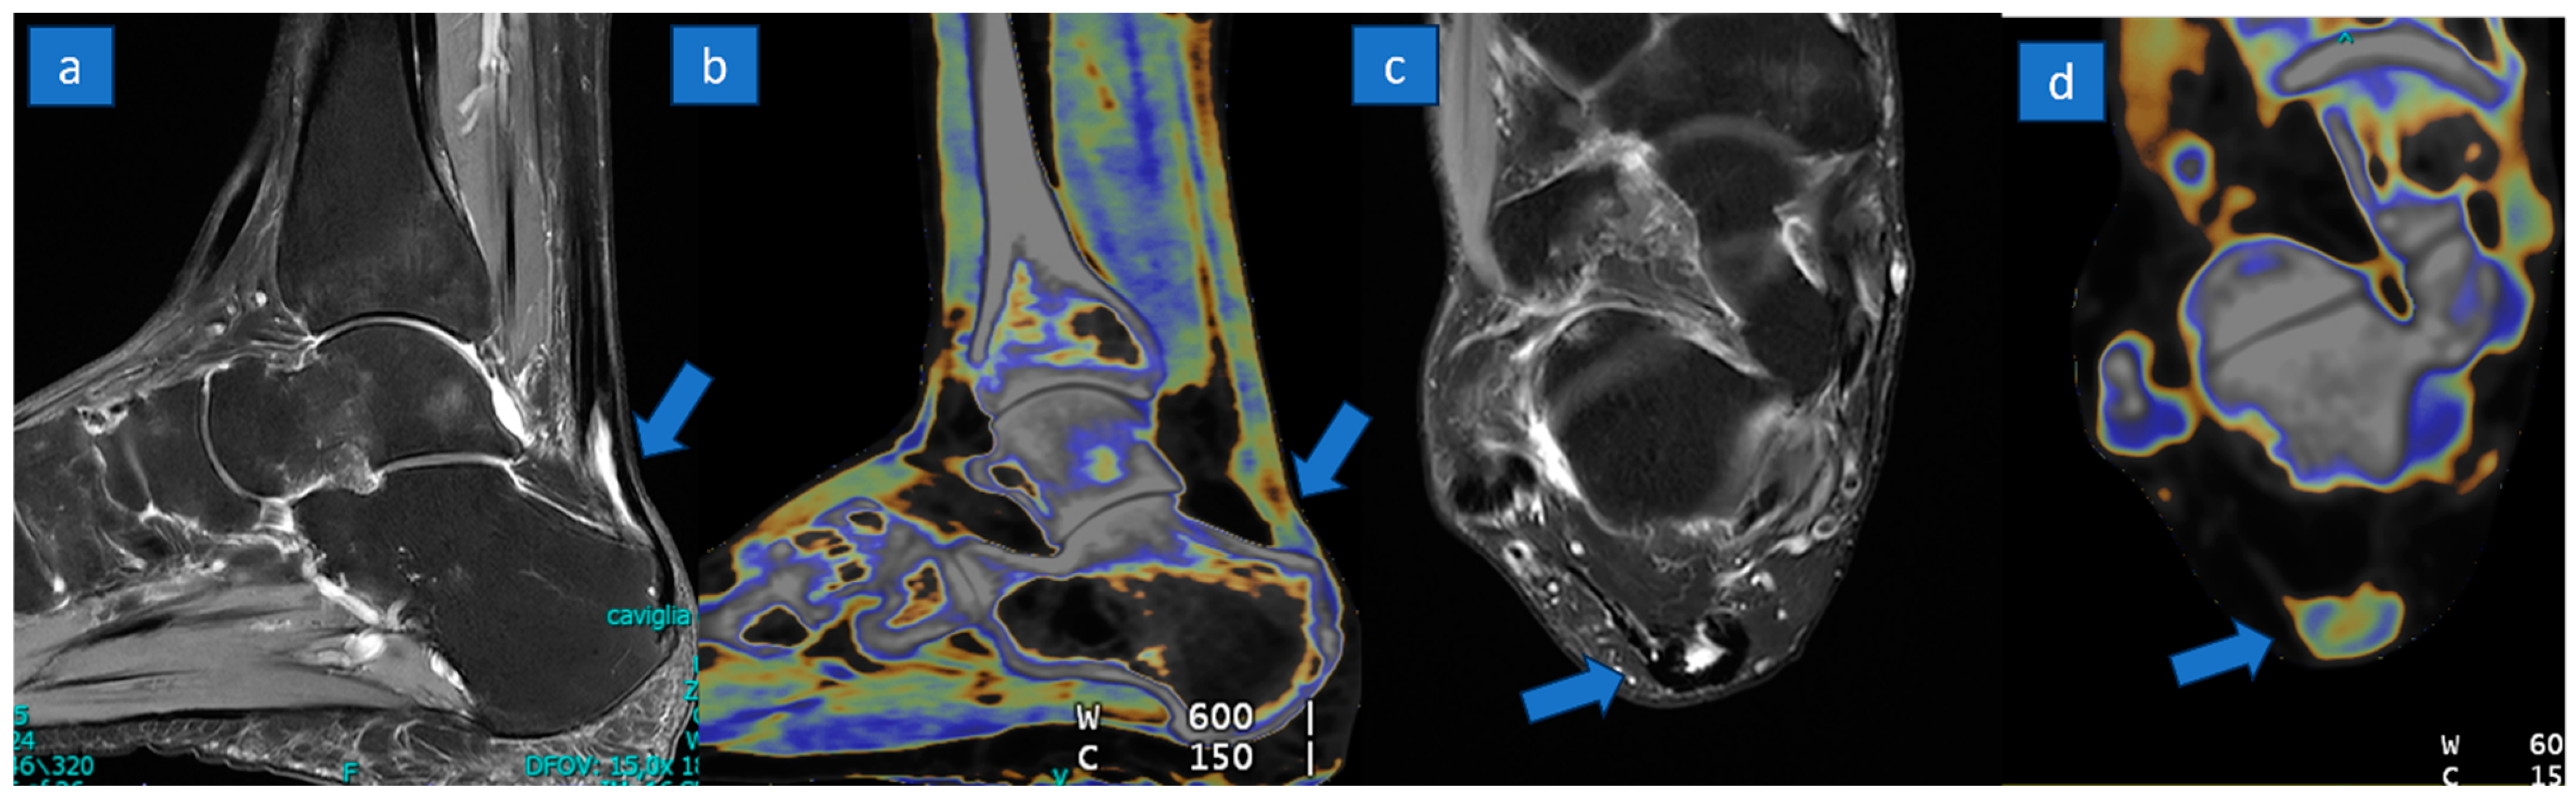

Figure 4.

A 55-year-old woman with a partial tear of the distal aspect of Achille’s tendon. A partial tear with partial tendon retraction (arrow) is depicted on sagittal PD Fat-saturated MR image (a); on the corresponding sagittal reconstructed DECT super-imposed color-coded image (b) there is the loss of normal tendon appearance, but it is not possible to rule out a complete tear. The partial, horseshoe-shaped anterior tear (arrow) is recognizable on the distal aspect with a very good correlation between MRI (c) and DECT (d) axial images.